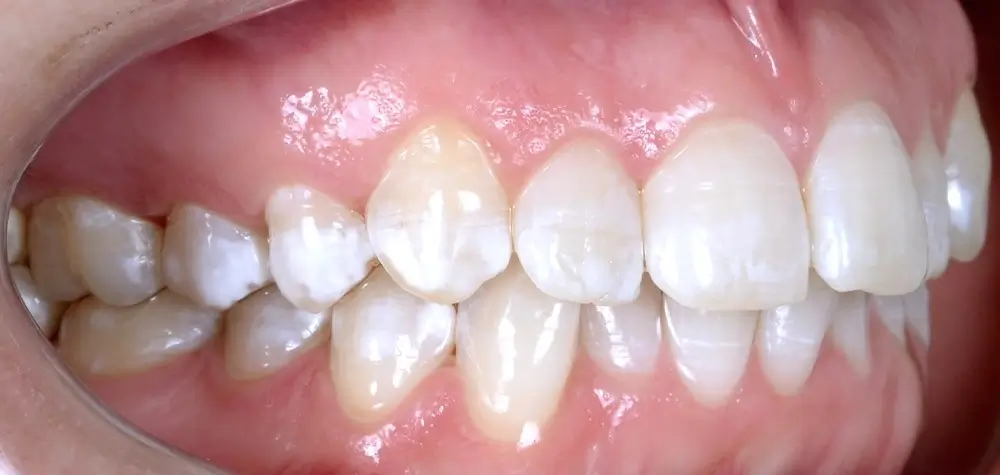

Кейс 1

Количество кап ВЧ 25

Количество кап НЧ 25

ДО

ПОСЛЕ